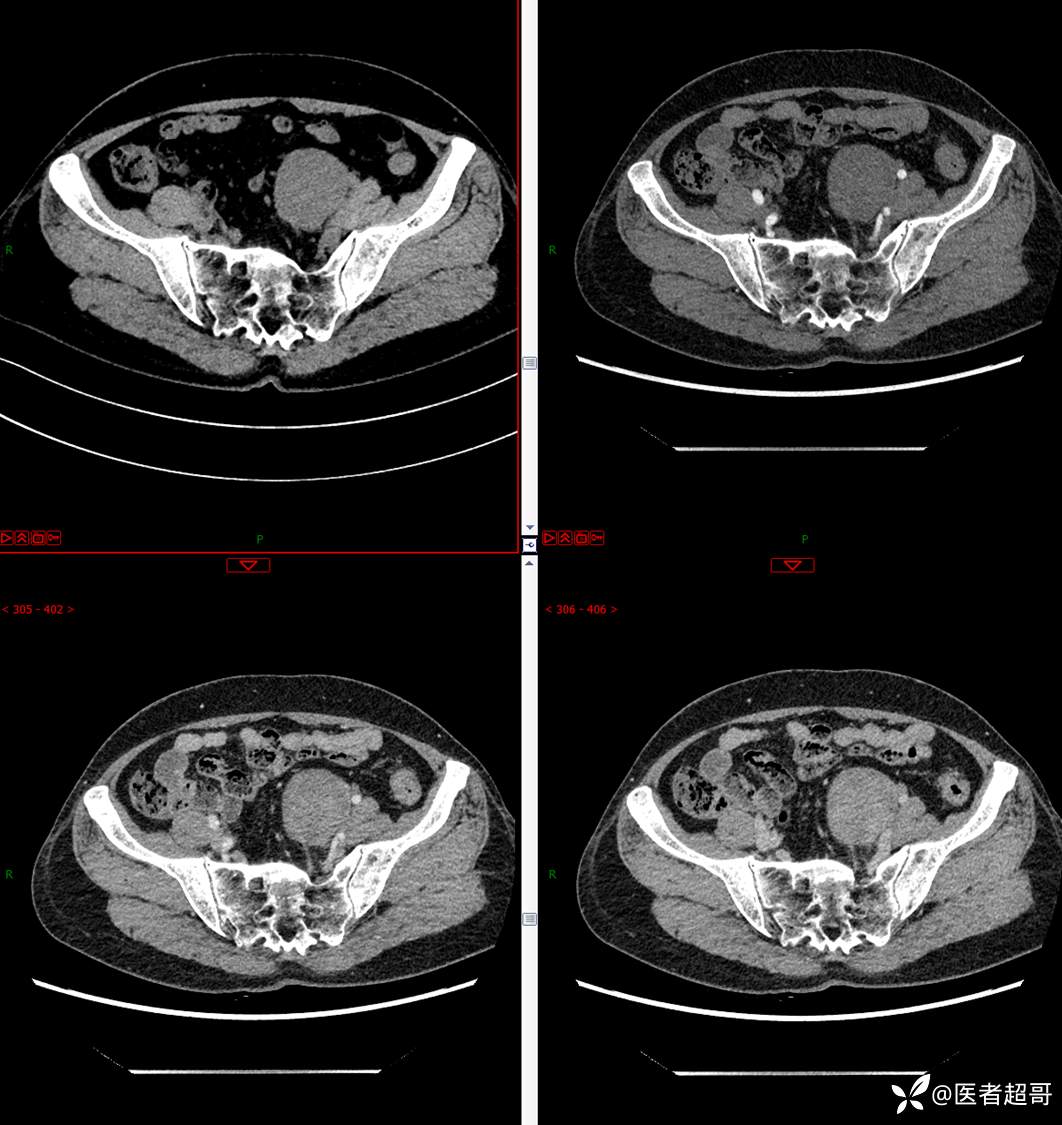

【影诊笔记559】查体发现右输尿管结石1周,发现腹膜后肿物,请分析,有病理!

•主 诉:查体发现右输尿管结石1周。

•现病史:患者1周前因小便不适来我院门诊行彩超检查提示右输尿管结石并右肾积水,伴腰疼,无血尿,无寒战,高热,患者求其进一步诊治,门诊以“右输尿管结石并右肾积水”收入院,患者自发病以来,神志清,精神可,饮食睡眠可,大便便秘,近期体重无明显增减。

•既往史:既往体健,否认高血压、糖尿病、心脑血管病等疾病史,否认肝炎、结核或其他传染病史及密切接触史,预防接种史不详,否认药物及食物过敏史,否认外伤史,10年在市立医院行结石手术治疗,否认输血史,其它无特殊。